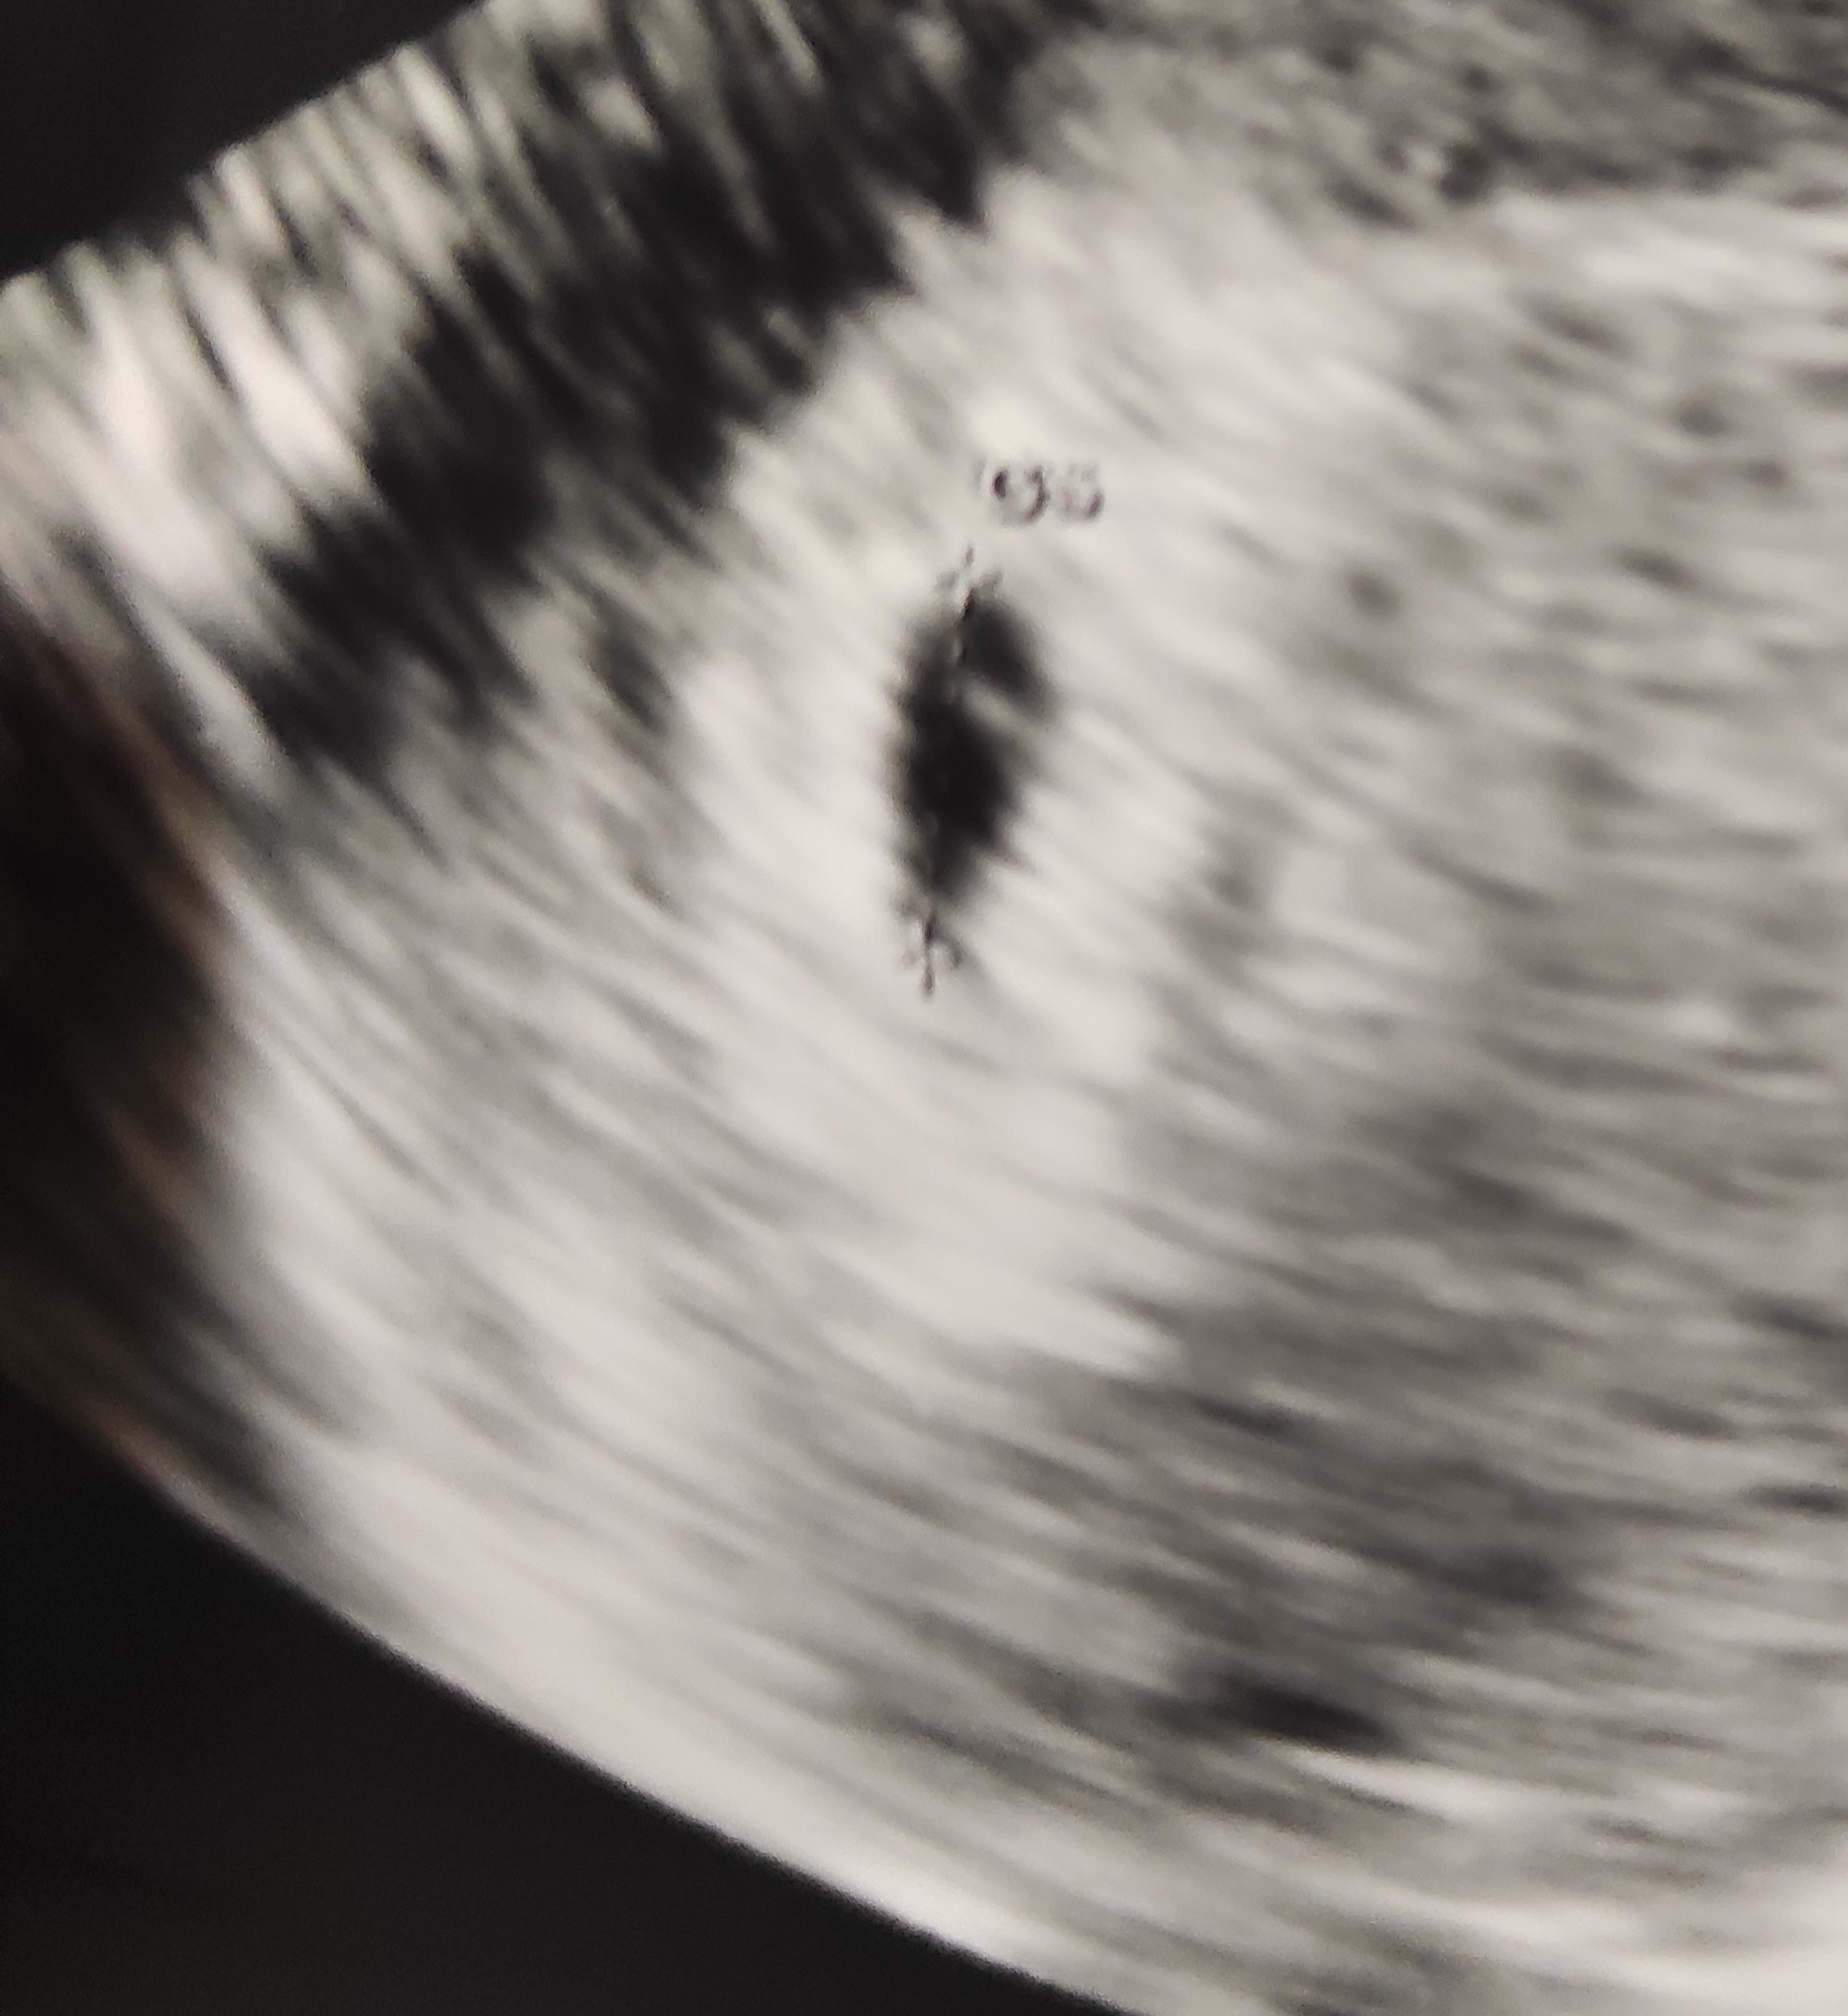

Poznajcie mojego małego fistaszka. Niestety trafiłam na jakiegoś marnego lekarza (mimo że prywatny) który stwierdził że nie da się określić daty porodu ani po zarodku bo jest za malutki ani po pęcherzyku chociaż pęcherzyk nie jest mały nie wiem zdziwiło mnie to ale powiedział że skoro mieliśmy monitoring to data porodu powinna być około 17 lutego. Cóż nie jestem może usatysfakcjonowana do końca ale cieszę się że go zobaczyłam ☺️☺️❤️❤️❤️ Teraz tylko spokojnie czekać do 5.07 i już na bank będzie serduszko. 😁.